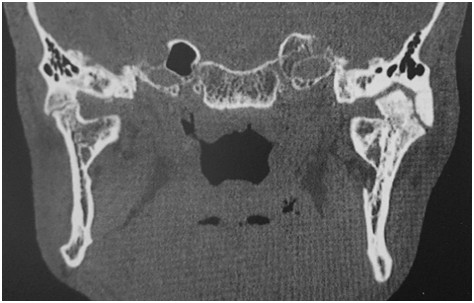

Rycina przedstawia czołowy skan z badania TK pacjenta, który przebył uraz głowy kilka lat wcześniej. Wskaż prawidłową interpretację tego obrazu: